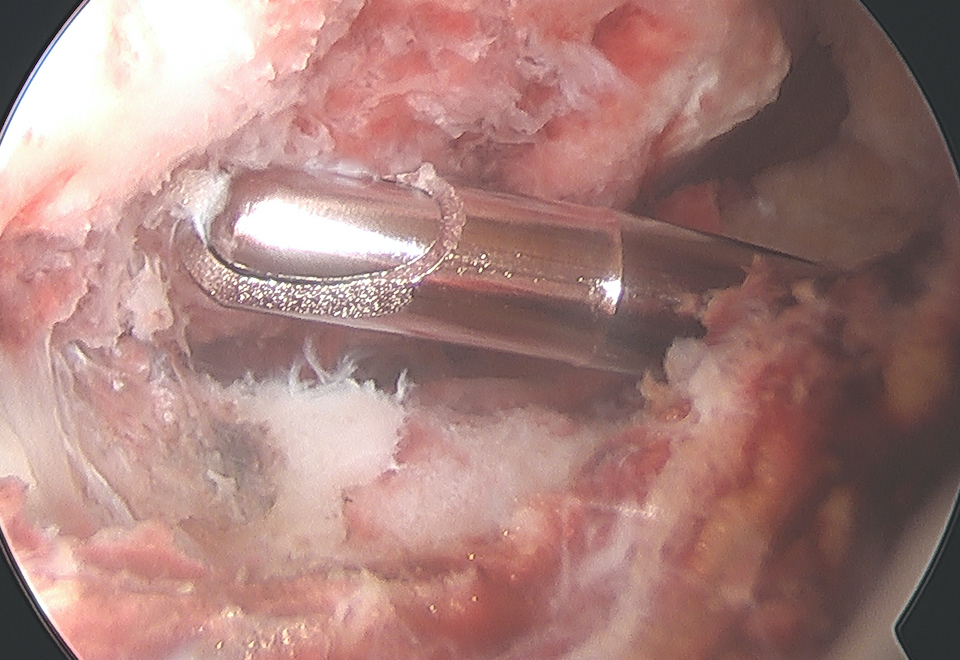

Arthroscopic suture fixation

Fragment flipped and insertion debrided Avulsion fragment reduction Passage of two loop sutures with scorpion

Technique

Clean haematoma, ensure can reduce fragment with probe

- can consider temporary fixation with K wire

- arthroscopic suture passer (i.e. arthrex knee scorpion)

- pass sutures x 2 through ACL above bony fragment

- cannulas can be useful for suture management